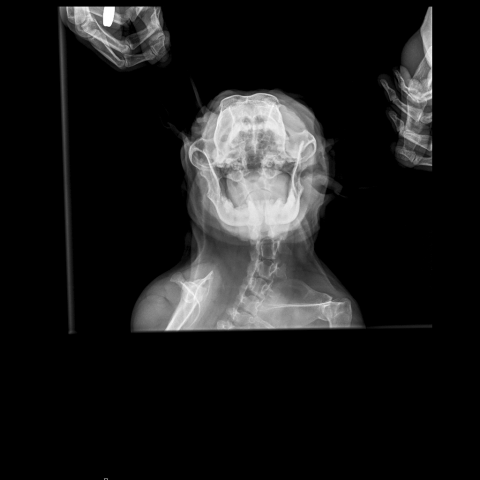

Снимки хорошие, качественные, но совершенно не информативные. На этих пленках патология не определяется. Но здесь нет снимка, который нужен обязательно - поясничный отдел позвоночника в прямой проекции (такой, как 3-й, но только не шея, а поясница).

Нет,наоборот.Собака сначала стала немного наклонять голову вправо.Когда были на консультации у окулиста,то он обратил внимание на это ,сказал,что есть какие-то изменения в области шеи.Я отсутствовала дома 2 недели.Приехала,собаку вообще не узнала.Крен головы вправо стал еще сильнее,передние ноги как-то ослабли.Она идет,может споткнуться,упасть.Сходили,сделали рентген.снимок.Поставили диагноз:атланто-аксиальная нестабильность шейного отдела,спондилоартроз. Проколола 5 дней:актовегин,папаверин,комбилипн,мидокалм,дексаметазон. Пока делала уколы и еще дней 5 после этого собаке стало легче,а потом опять вернулись к тому, что было.На консультации врач сказал,что дальше просто колоть преднизалон. Я уехала к другому врачу,тот сделал снимки,которые я Вам отослала.Сказал, что диагноз не подтверждает,на пальцах показал, что со спинным мозгом все нормально.С помощью какой-то процедуры (бумаги на работе)обнаружил перфорацию барабанной перепонки.Выписал лечение:цефтриаксон,циклоферон,цебролизин(колола 2 дня,стало хуже),комбилипен.В уши-изотик.Сказал,что может быть у собаки был инсульт.Собаке от лечения хуже.Вот такие дела.